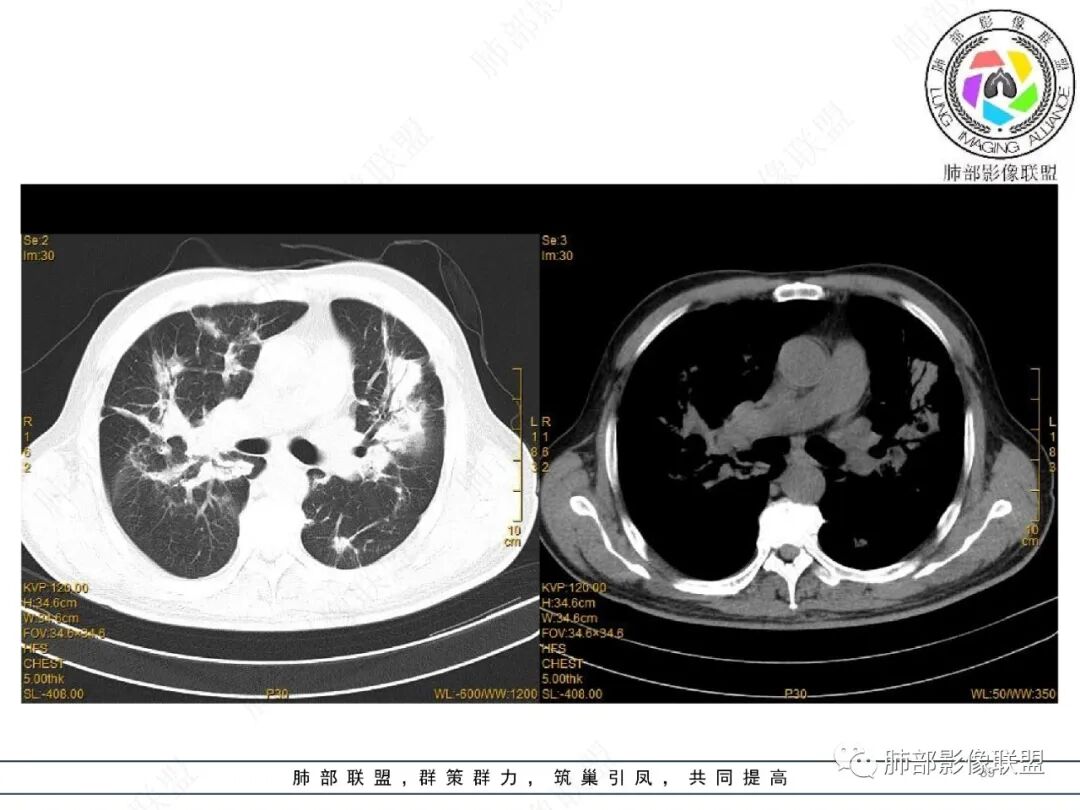

2022.2.17CT显示两肺中内带多发结节影、斑片影、条索影,部分病灶侧向融合与胸膜平行。部分病灶沿着支气管血管束分布、其内支气管稍扩张。部分病灶呈反晕征。大部分病灶边界显示清晰,部分病灶周围可见边界不清的GGO。2022.4.12CT显示两肺中内带多发结节影、条索状、条带状高密度影,边界收缩平直凹陷,大部分病灶沿着支气管血管束分布,亦有位于胸膜下侧向融合与胸膜平行的病灶。总体与第一次CT对比两肺病灶明显吸收。